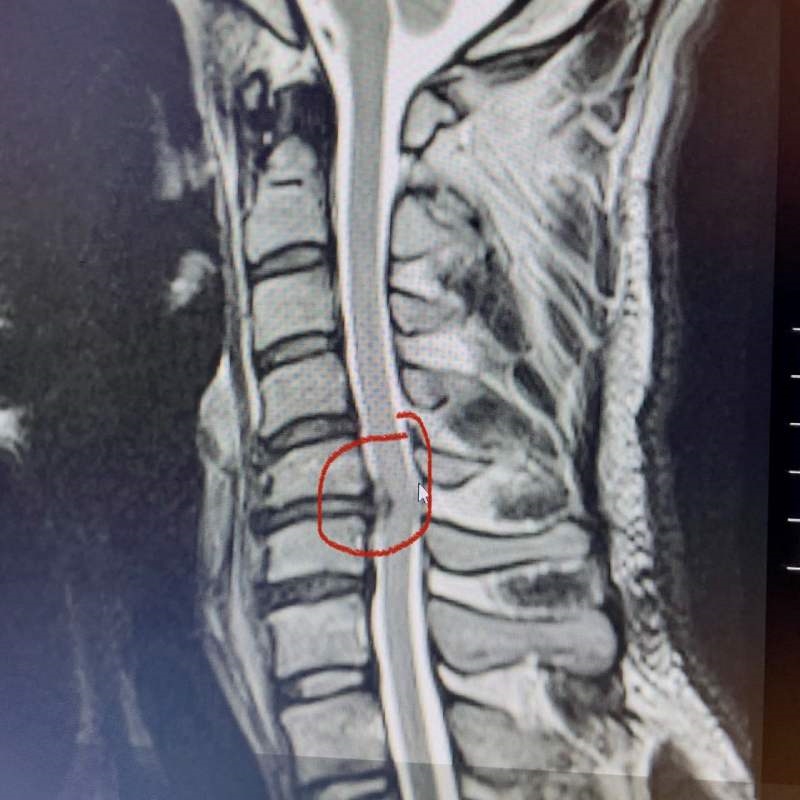

另一則新聞則是中國籍綜合格鬥選手李景亮,因為頸椎神經根壓迫,可能會被迫中斷職業生涯。李景亮長期已有頸部不適,應是長期練習角力及柔術累積傷害且恢復不足的結果,暫時無法出賽,且有面臨開刀的可能性。

圖/頸椎神經根病變。圖片取自李景亮TWITTER